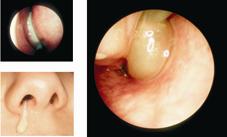

其中又以慢性鼻竇炎最難治療,且藥物治療效果較差。慢性鼻竇炎的症狀包括:顏面部疼痛、鼻塞、流膿鼻涕、嗅覺減退(圖一)鼻竇炎手術的最新進展 「電磁式鼻竇導航手術」(相關圖片);甚至連其他非鼻部直接相關的症狀,如頭痛、發燒、口臭、牙齒疼痛、疲倦以及慢性咳嗽等,都有可能是因鼻竇炎所導致。除了病患因上述的症狀,影響生活品質以外,偶而亦有嚴重的鼻竇炎併發症案例,例如:眼眶蜂窩組織炎、眼膿腫、失明、腦膜炎、腦膿腫等,因而千萬不可輕忽。